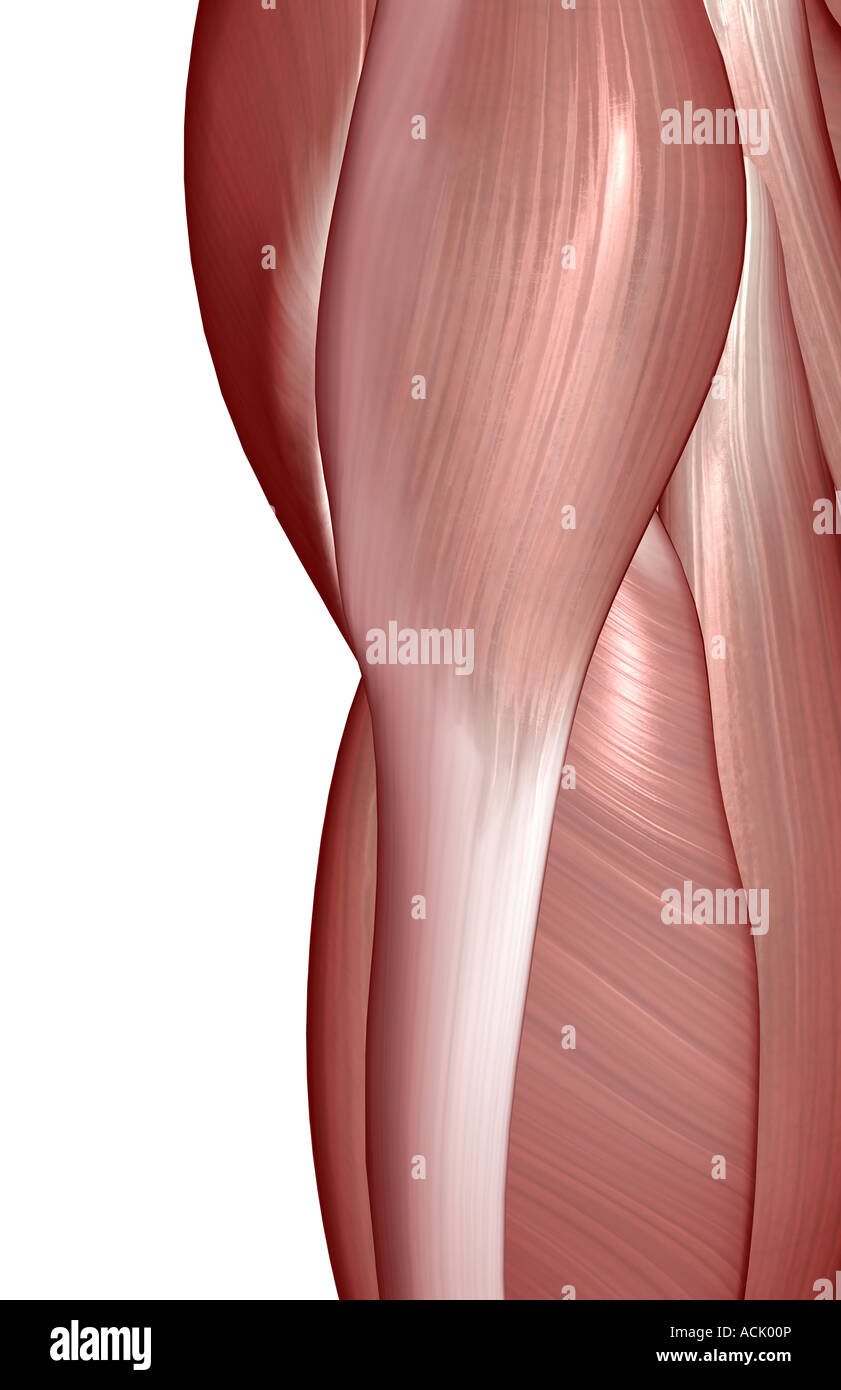

The muscles of the hip Stock Photohttps://www.alamy.com/image-license-details/?v=1https://www.alamy.com/stock-photo-the-muscles-of-the-hip-13174341.html

The muscles of the hip Stock Photohttps://www.alamy.com/image-license-details/?v=1https://www.alamy.com/stock-photo-the-muscles-of-the-hip-13174341.htmlRFACK00P–The muscles of the hip